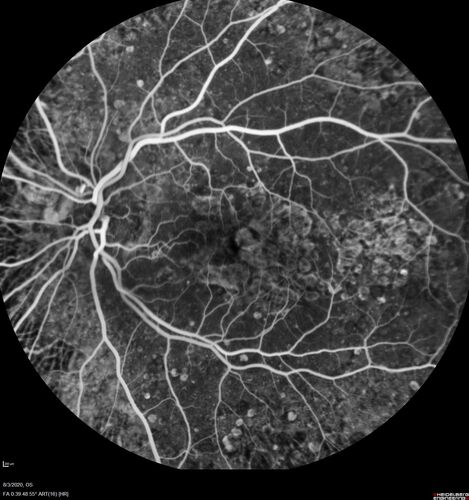

Dry AMD geographic atrophy and cystoid macular edema

79 year old vision is in for a checkup with no visual complaints in the left eye.  This is her better eye.  VA 20/200 OD, 20/50 OS.  3 years ago she had a CRVO in the left eye.  She is also diabetic for 20 years, has carotid insufficiency and anemia.  Left eye shows CME.  This was not treated and the vision improved to 20/40 over the next year although mild edema persisted.